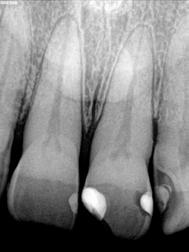

A mikrotöltésű kompozitok röntgenelnyelőek, különösen a mikrohíddal (13. ábra) összehasonlítva, amely a röntgenfelvételeken diagnosztikai problémát jelenthet, különösen az interproximális területeken. Mivel eredendően gyengék, a mikrotöltelékeket nem szabad olyan területekre helyezni, amelyek okklusális terhelésnek lesznek kitéve (6. ábra). Csak kis mennyiséget kell használni, az okklusális terhelés a sokkal erősebb mikrohibrid kompozitra marad.

Egy páciens elégedetlen volt a 8. fog incisofaciális felszínén lévő kéthetes restaurációval, mert úgy gondolta, hogy a központi metszőfogak nem illeszkednek egymáshoz. A vizsgálat során megállapították, hogy bár az egyszínű kompozit valóban megegyezett a fog alapszínével, további színre (árnyalatra) volt szükség a szomszédos fog utánzásához (4. ábra).

A fogakat nehéz latexmentes gumidámmal (Isodam, 4D Rubber) izolálták. A meglévő kompozitot eltávolítottuk; egy kromatikus mikrotöltésű kompozitot helyeztünk fel, és egy fehér színt (Creating Color, Cosmedent) vittünk fel egy #8-as K-résszel, vízszintes mozgással, hogy a vízszintes mintázatot lemásoljuk (5. ábra), ezután egy akromatikus mikrotöltésű kompozitot adtak hozzá. A 6. ábra az azonnali posztoperatív eredményt mutatja, a 7. ábra pedig a négyéves utóvizsgálatot, amely a mikrotöltött kompozit megmaradt fényét mutatja.